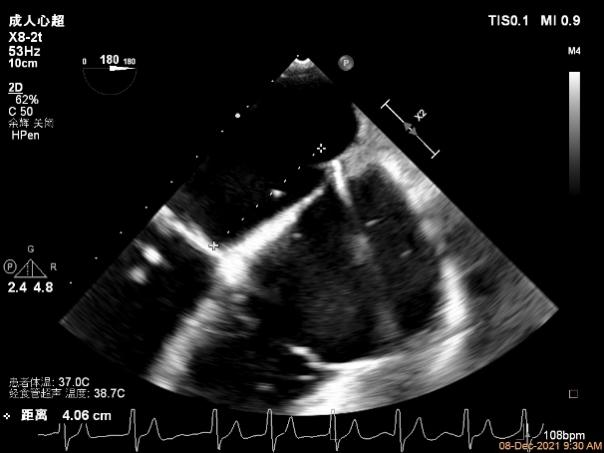

患者高龄、心衰时间较长、体型瘦小虚弱,无法耐受外科手术治疗,在门诊和入院初期评估时,由风湿性+功能性+退行性等多种原因导致的二尖瓣病变病理生理机制也给经导管介入治疗带来极大的挑战。门诊经胸超声心动图提示风湿性改变伴有轻度二尖瓣狭窄是传统意义上经导管缘对缘修复技术的禁忌,脱垂区后叶因AFMR参与被牵拉较短也是TEER的技术瓶颈。但患者反复心衰发作,病情恶化迅速,积极治疗重度的二尖瓣反流将是改善患者预后的一线生机。因此入院后我们通过经食道超声给这位患者进行了细致的评估后发现,患者的确有二尖瓣瓣叶增厚的改变,跨瓣压差在3-5mmHg,二尖瓣瓣口面积在4.43cm²,并没有明显的开放受限,瓣膜面积相对来说是TEER治疗的临界水平,后叶长度约7mm,尽管相对较短,在我们前期的TEER治疗患者中也可以达到充分的钳夹长度。因此经过心脏团队反复的综合评估,认为该患者有TEER治疗成功的机会,在充分药物治疗,患者心衰症状改善且病情平稳后,在患者以及家属强烈要求下,我们积极完善术前准备,择期行TEER治疗。

术前超声评估结果

术前超声诊断

Qlab软件勾画估测瓣口面积约:4.42cm²

二尖瓣口平均跨瓣压差:5mmHg